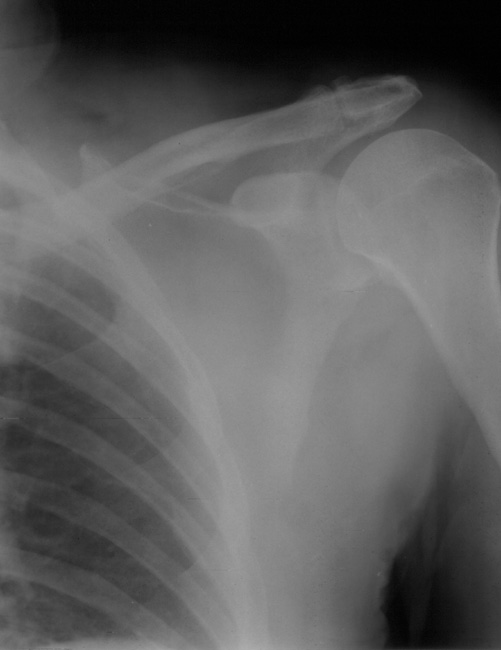

To provide an opportunity for the comparison of image scanning techniques, we are posting in the "Digital Images" forum of the HWB Home Page (http://www.hwbf.org/hwb/) an AP Shoulder film scanned with a $16,000 Howtek Scanmaster DX Xray scanner and a $200 "Snappy" video digitizer. The "Snappy" plugs into the video port of a camcorder or VCR. JPEG compression of either 5:1 or 10:1 are applied to the scans. We would be interested in any feedback with respect to the diagnostic quality of these images.

Click images to enlarge.ROW 1: JPEG 5:1 compression

2)